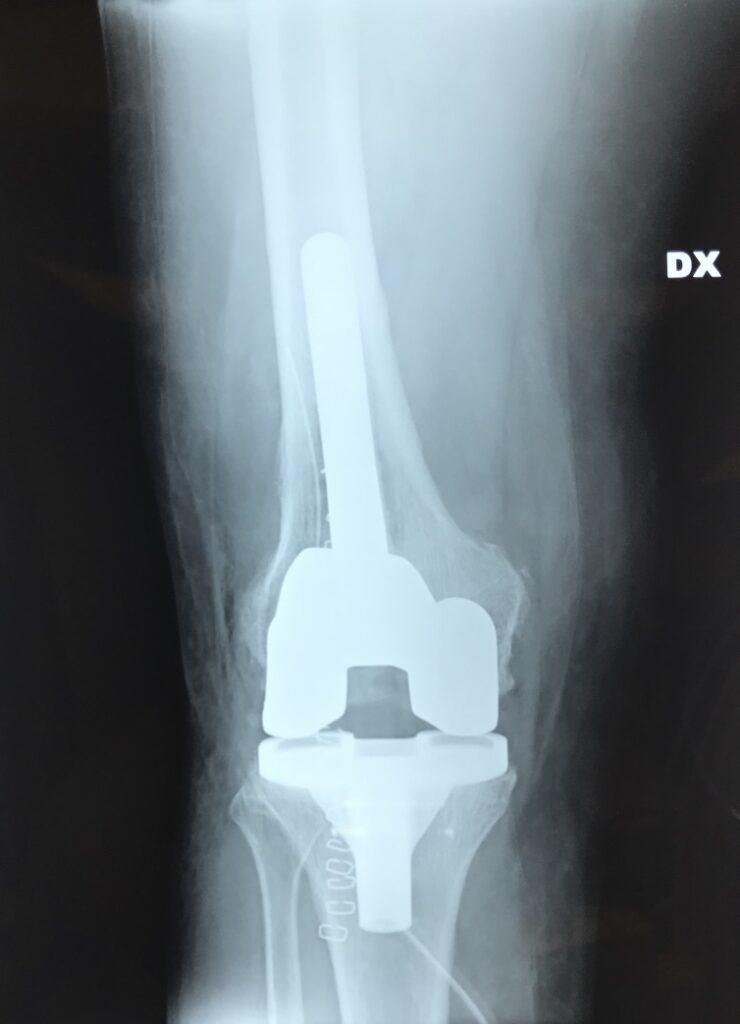

- Il ginocchio di Giuseppe, ormai nostro Amico : operato al Nord , si infetta . Tutti lo rifiutano. Nessuno lo vuole accogliere. Il Nostro Reparto , il Nostro Ospedale , SI! Una storia……per fortuna a lieto fine.

radiografie con la protesi di ginocchio reimpiantata : oggi Giuseppe guida la Sua auto sportiva.